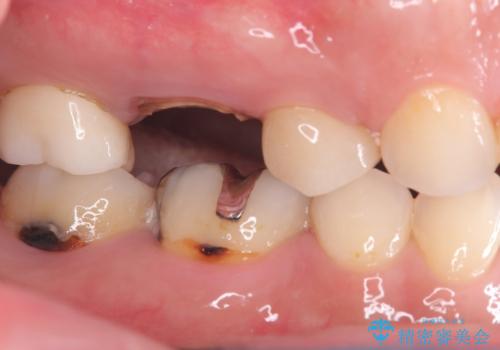

- 右上の6番の奥歯の痛みを主訴に来院されました。精密検査の結果、根管内を歯科用顕微鏡で確認したところ、肉眼では見えないクラック(ひび割れ)が発見されました。このクラックが痛みの原因であり、将来的に歯の保存が難しいと判断。患者様と話し合い、歯を残すことを諦め、抜歯と同時にインプラントを埋入する抜歯即時埋入インプラントによる治療計画を立案しました。これにより、治療期間と身体への負担を最小限に抑え、確実な解決を目指しました。

今回の治療では、まず原因となっていた奥歯を慎重に抜歯し、その直後にインプラントを埋入しました。この抜歯即時埋入により、抜歯からインプラント埋入までの期間を省き、骨の吸収を最小限に抑えられました。治療後は痛みや腫れも少なく、患者様は快適に過ごしていただけました。最終的に、わずか3ヶ月でセラミッククラウンを装着。機能性と審美性を兼ね備えた新しい歯により、長年の痛みが解消され、快適な食生活を取り戻していただけました。